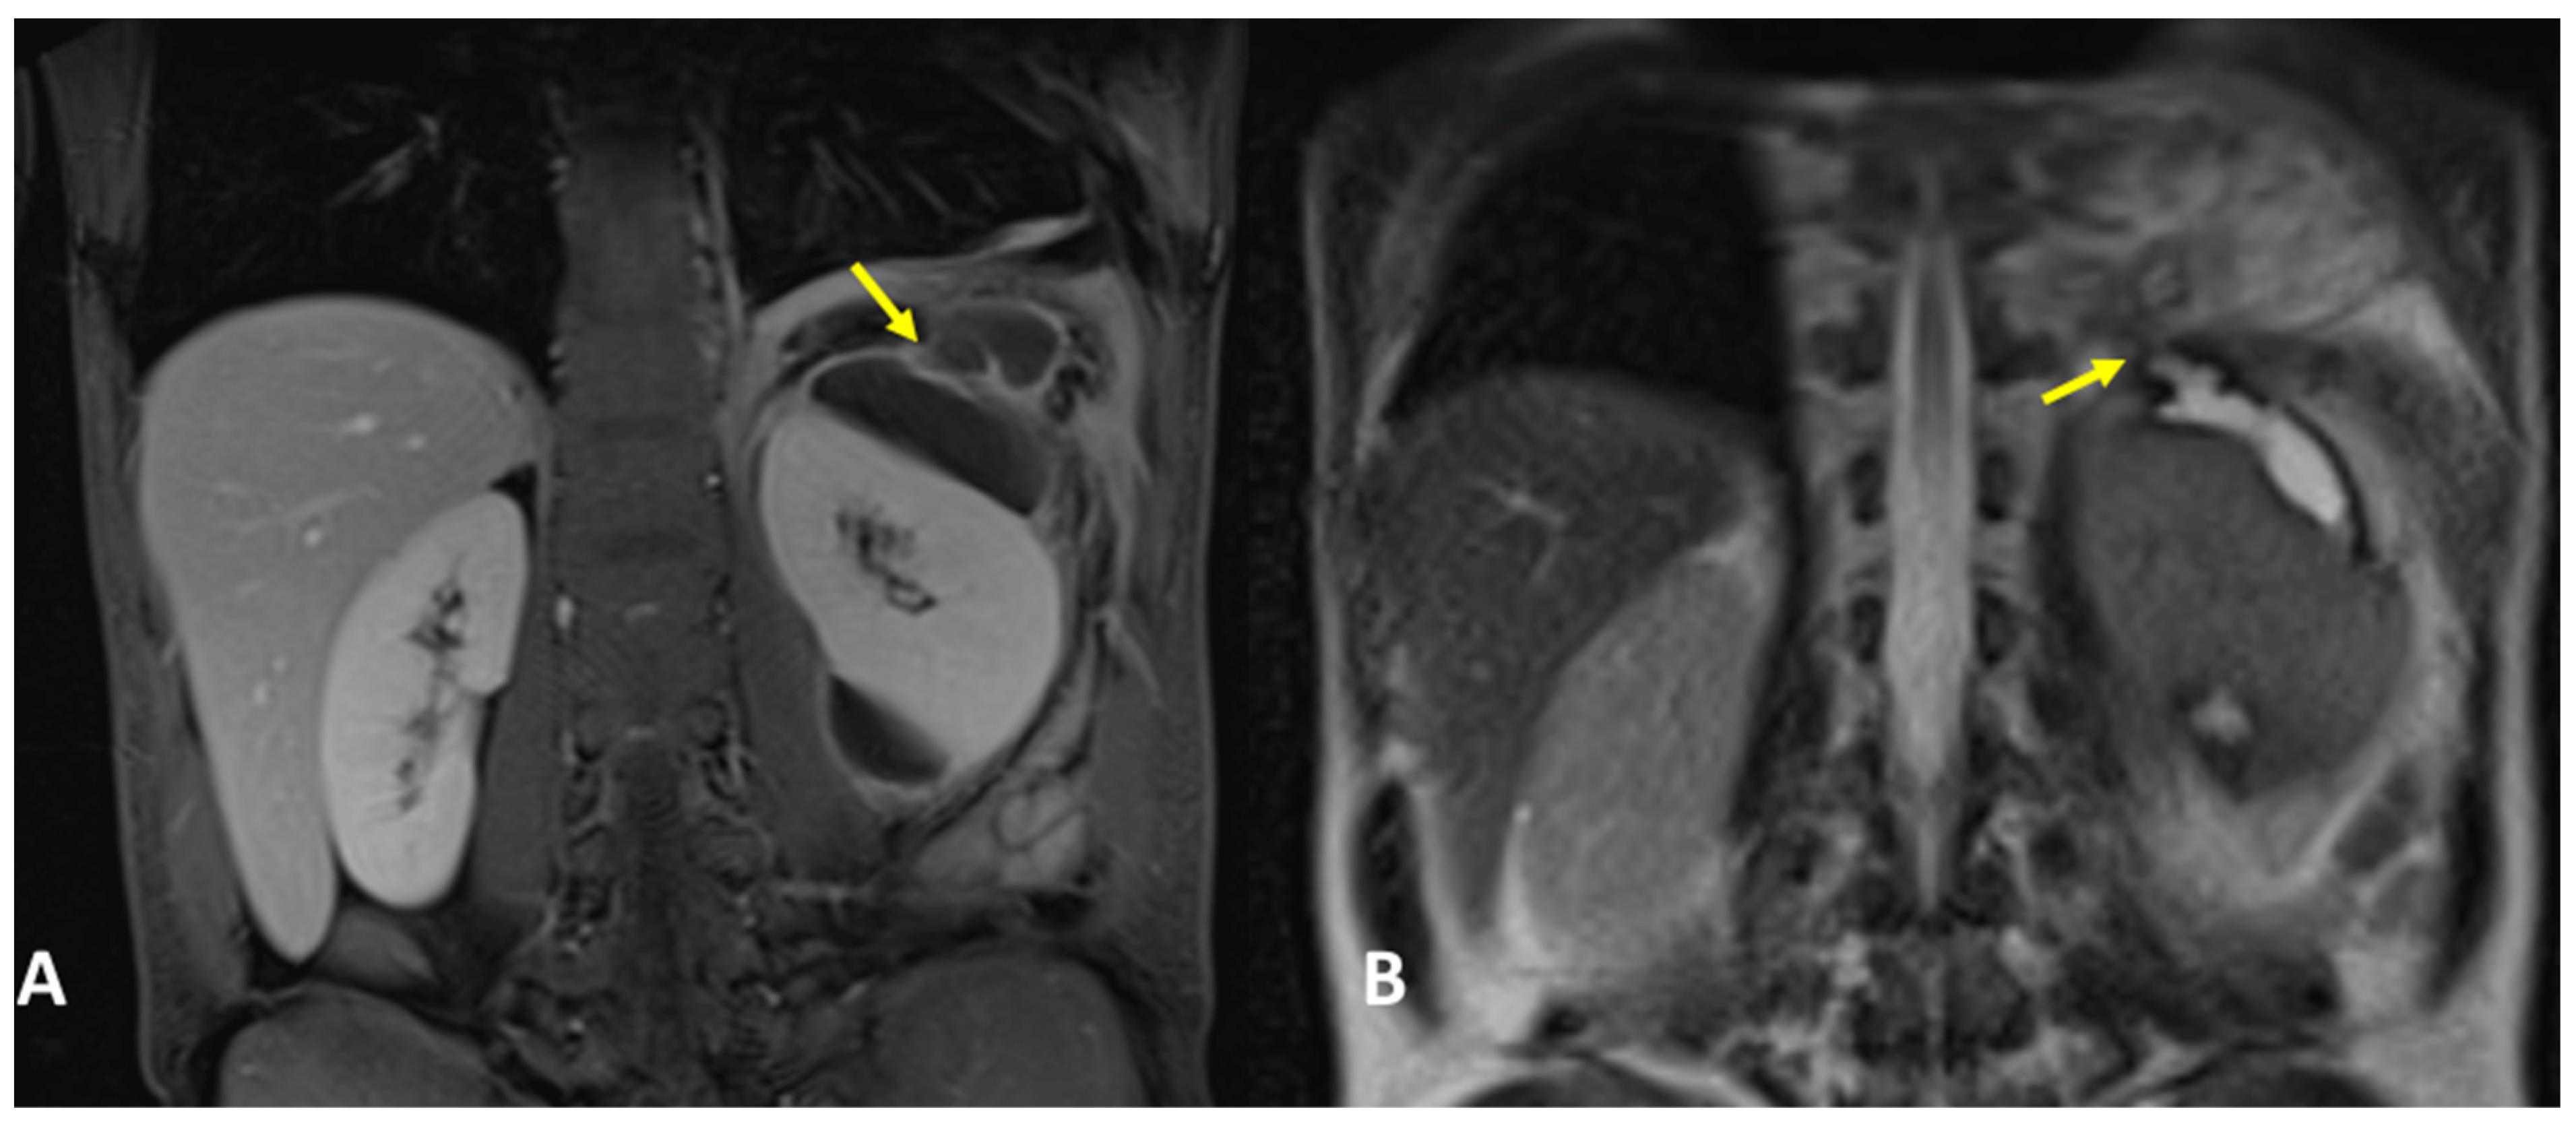

A 31-year-old woman, with a history of a previous splenectomy performed 10 years ago, was referred to an ER setting with fever and diffuse thoraco-abdominal pain and was not responding to 15-day antibiotic therapy. Physical examination revealed upper intense abdominal pain and diminished breath sounds over the left hemithorax. Laboratory routine tests showed mild neutrophilia, increased CRP, and severe increase in lipase and amylase levels, notably pancreatic amylase. The patient underwent chest X-ray that showed a PNX on the left side with left lower lobe parenchymal consolidation. The pneumothorax was drained. Subsequently, the patient underwent contrast-enhanced thoraco-abdominal CT confirming left pneumothorax, left pleural empyema, and multiple communicating large pancreatic pseudocysts, with a fistulous tract through the left diaphragm (Figure 7A–C). Therefore, a diagnosis of PPF was suspected, and contrast-enhanced MRI confirmed the same findings (Figure 8A,B). The patient immediately underwent drainage of the abdominal collections and pseudocysts located in the pancreatic tail and left subdiaphragmatic lodge. Antibiotic therapy was started. In the following days, the patient underwent surgery to evacuate the empyema, pneumolysis, and placement of double pleural drainage, as well as closure of the transdiaphragmatic fistula.

Figure 8.

(A,B) Contrast-enhanced MRI, coronal planes, and CE T1- (A) and T2-weighted sequences (B) (same patient as Figure 7). MRI confirmed a left pleural empyema and multiple pancreatic pseudocysts located between the diaphragm, the pancreas tail, and the left kidney. The fistulous tract was detected (arrows).